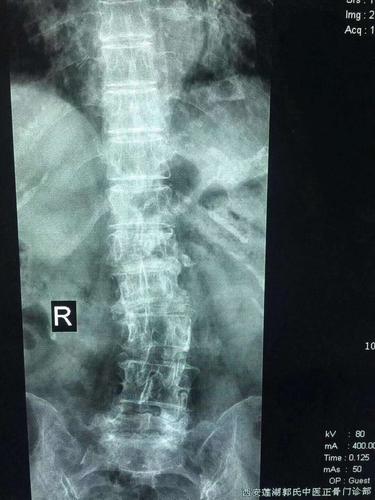

腰5楔型变 写美篇 x线片显示:腰5楔型变,腰椎侧弯,腰椎明显骨质增生

腰椎骨质增生.png

腰椎骨质增生